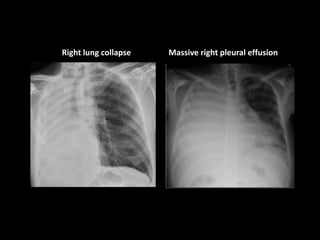

Right lung collapse Massive right pleural effusion